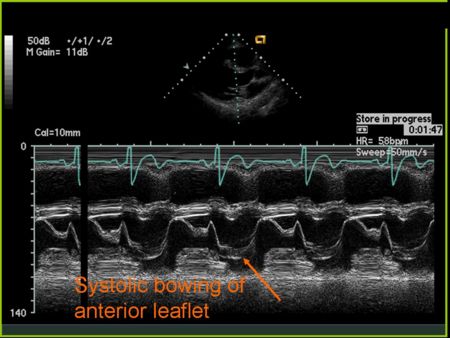

M Mode in Mitral Valve Prolapse

- Systolic bowing of the posterior mitral valve leaflet

M Mode in Hypertrophic Cardiomyopathy

- Septal hypertrophy

- Systolic anterior motion (SAM) of the anterior mitral valve leaflet